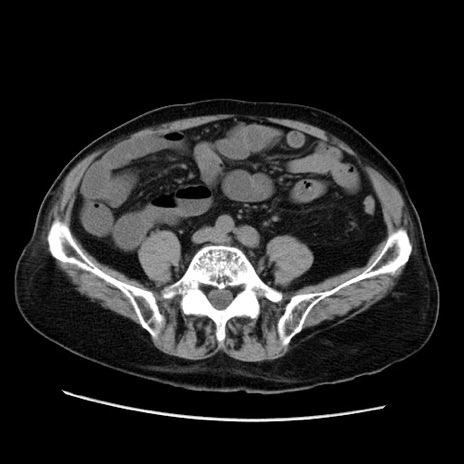

症例21(横断像)

【症例】70歳代男性

【主訴】腹痛

【現病歴】肝硬変・肝細胞癌にてかかりつけの方。約9時間前に食後より腹痛出現。症状が徐々に増悪し、嘔吐出現したため来院。

【既往歴】肝硬変、肝細胞癌(RFA、TACE後)

【身体所見】意識清明、表情苦悶様、BT 36℃、BP 129/78mmHg、P 88bpm、SpO2 97%(RA)、右上腹部から心窩部にかけて圧痛あり、反跳痛なし、筋性防御あり。

【データ】WBC 5800、CRP 0.16